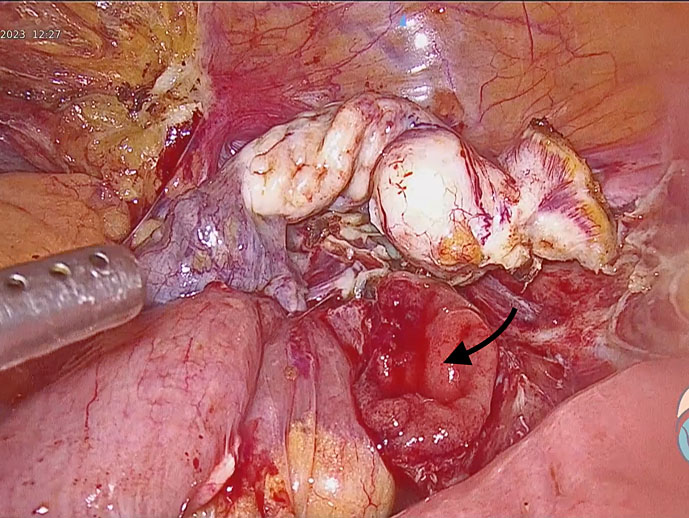

Bowel injury

If the primary trocar enters the bowel, identified on creation of pneumoperitoneum, the trocar should not be removed immediately. Instead, gas inflow should be stopped and the abdomen accessed through an alternate port, such as Palmer’s point. Using a 30° laparoscope, the trocar in the bowel can be visualized. It should be ascertained whether the injury involves the small or large bowel or, less likely, is a through-and-through injury. After access via additional ports, the primary trocar should be removed from the bowel. The defect is usually amenable to primary closure in two layers (Figure 19). The intended surgical procedure can then be completed and postoperatively the patient kept nil by mouth. A drain may be placed to allow early detection of any leakage. When there is no evidence of peritonitis or leakage and peristalsis has resumed, oral liquids can be gradually reintroduced. The involvement of an experienced surgeon, administration of potent broad-spectrum antibiotics and adequate intravenous fluid management are critical for optimal outcomes.

19

Bowel injury identified intraoperatively. Bowel mucosa can be seen to be everted (arrow).